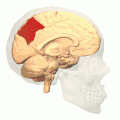

![]() Medial surface of left cerebral hemisphere. (Precuneus visible at top left.) (Anterior to the right.) | |

![]() Sagittal MRI slice with the precuneus shown in red. (Anterior to the left.) | |